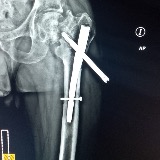

Hi friends Our beloved Elias, a dedicated brother, loving husband, and the cornerstone of our family, is in urgent need. After a devastating motorcycle accident, his life took an unexpected turn, leaving him in need of emergency surgery to save his leg.

The medical expenses are overwhelming, especially since Elias does not have health insurance to cover the costs. This surgery is crucial not just to save his leg, but to help him return to the life he cherishes and to the people who love him dearly.